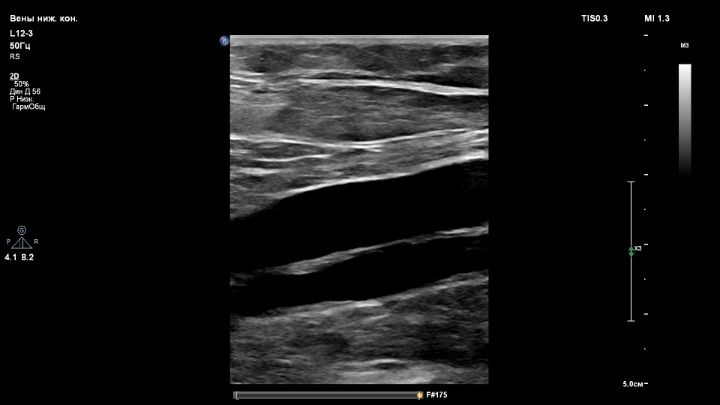

Подколенная вена без тромба, один пациент, три линейных датчика.

1. Датчик L12-3

- вены нижних конечностей для датчиков L12-3 и eL18-4;

Глубина сканирования одинаковая, 5 см.

Во-первых, датчик L12-3 всё же лучше для сосудов (вены и артерии конечностей, БЦА). Когда сравниваешь на одном пациенте, есть разница. Датчик L12-3 с более ясной картинкой. Если увеличить Gain на датчике eL18-4, пойдут помехи.

Но при работе на аппарате с 3-мя линейками, сравнивая их, я всё же для вен беру датчик L12-3.